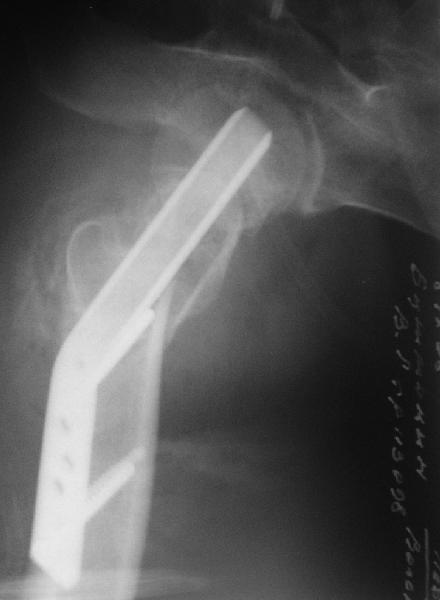

[Ortho] Нелеченный перелом шейки бедра

Приветствую всех. Спасибо за активное участие в обсуждении. Выбрали вариант с остеотомией.

Снимки в приложении.

Имя     : get_image1.jpg